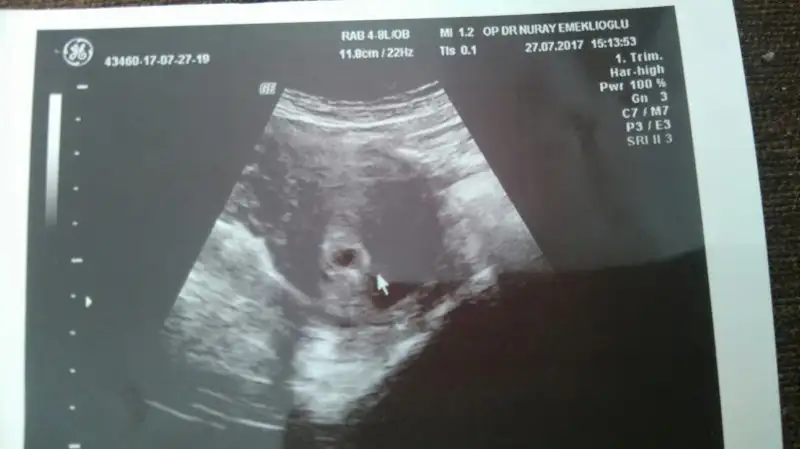

Boş bile olsa 11,8 cm çok büyük kese için orda mm yazsa doğru olabilirdi. Ben geçen gittiğimde keseyi ölçmedi bebeği gördüğümüz için ama ikinci bir kese vardı boş onu ölçtü 11,1 mm idi. Umarım herşey yolundadır.

Kızlar ben iyice , pskopata bağladım. Forumda başka bi konuya yorum yaparken bir arkadaş ultrson fotosuna bakmış o farkettirdi. Kese boyutunu ben mm olarak görmüştüm. Cm yazıyor deyince baktmki evt 11.8 cm yazıyo. Böyle bir durumda kese boyutysa bu oldukça büyük değilmi?? :KK43: bi bakarmısıEki Görüntüle 2027018 nız.

Dur hemen korkma bunun ihtimali Yok matematiğe aykırı ben kendi ultrason fotoğrafıma bakıcam sağ alt köşede yazıyor bende doğrusu benimki 6 haftalıkken 5.3 cm miş :) korkma panik yapma dikkatli ol sadece ve bol bol dua et

canım korkma o kese boyutu degil. dedikleri gibi keseyi genelde gs diye gösteriyor. senin resminde görnmüyor ya ölçmedi ya foto tam değil. bende de 6.5 cm yazıyor orası. belki rahim kalınlııgı falandır ama eminim kese değil o

Evet arkadaşlar sayesinde öğrendik :) foto tam ama dediğin gibi ölçüm yapmamış sanırım. Yazmıyo çünkü. Teşekkür ederiimm cvp için ;)

Canını sıkma canım kese ölçüsü olsa gs yazar yanında hem kese o kadar imkansız olması